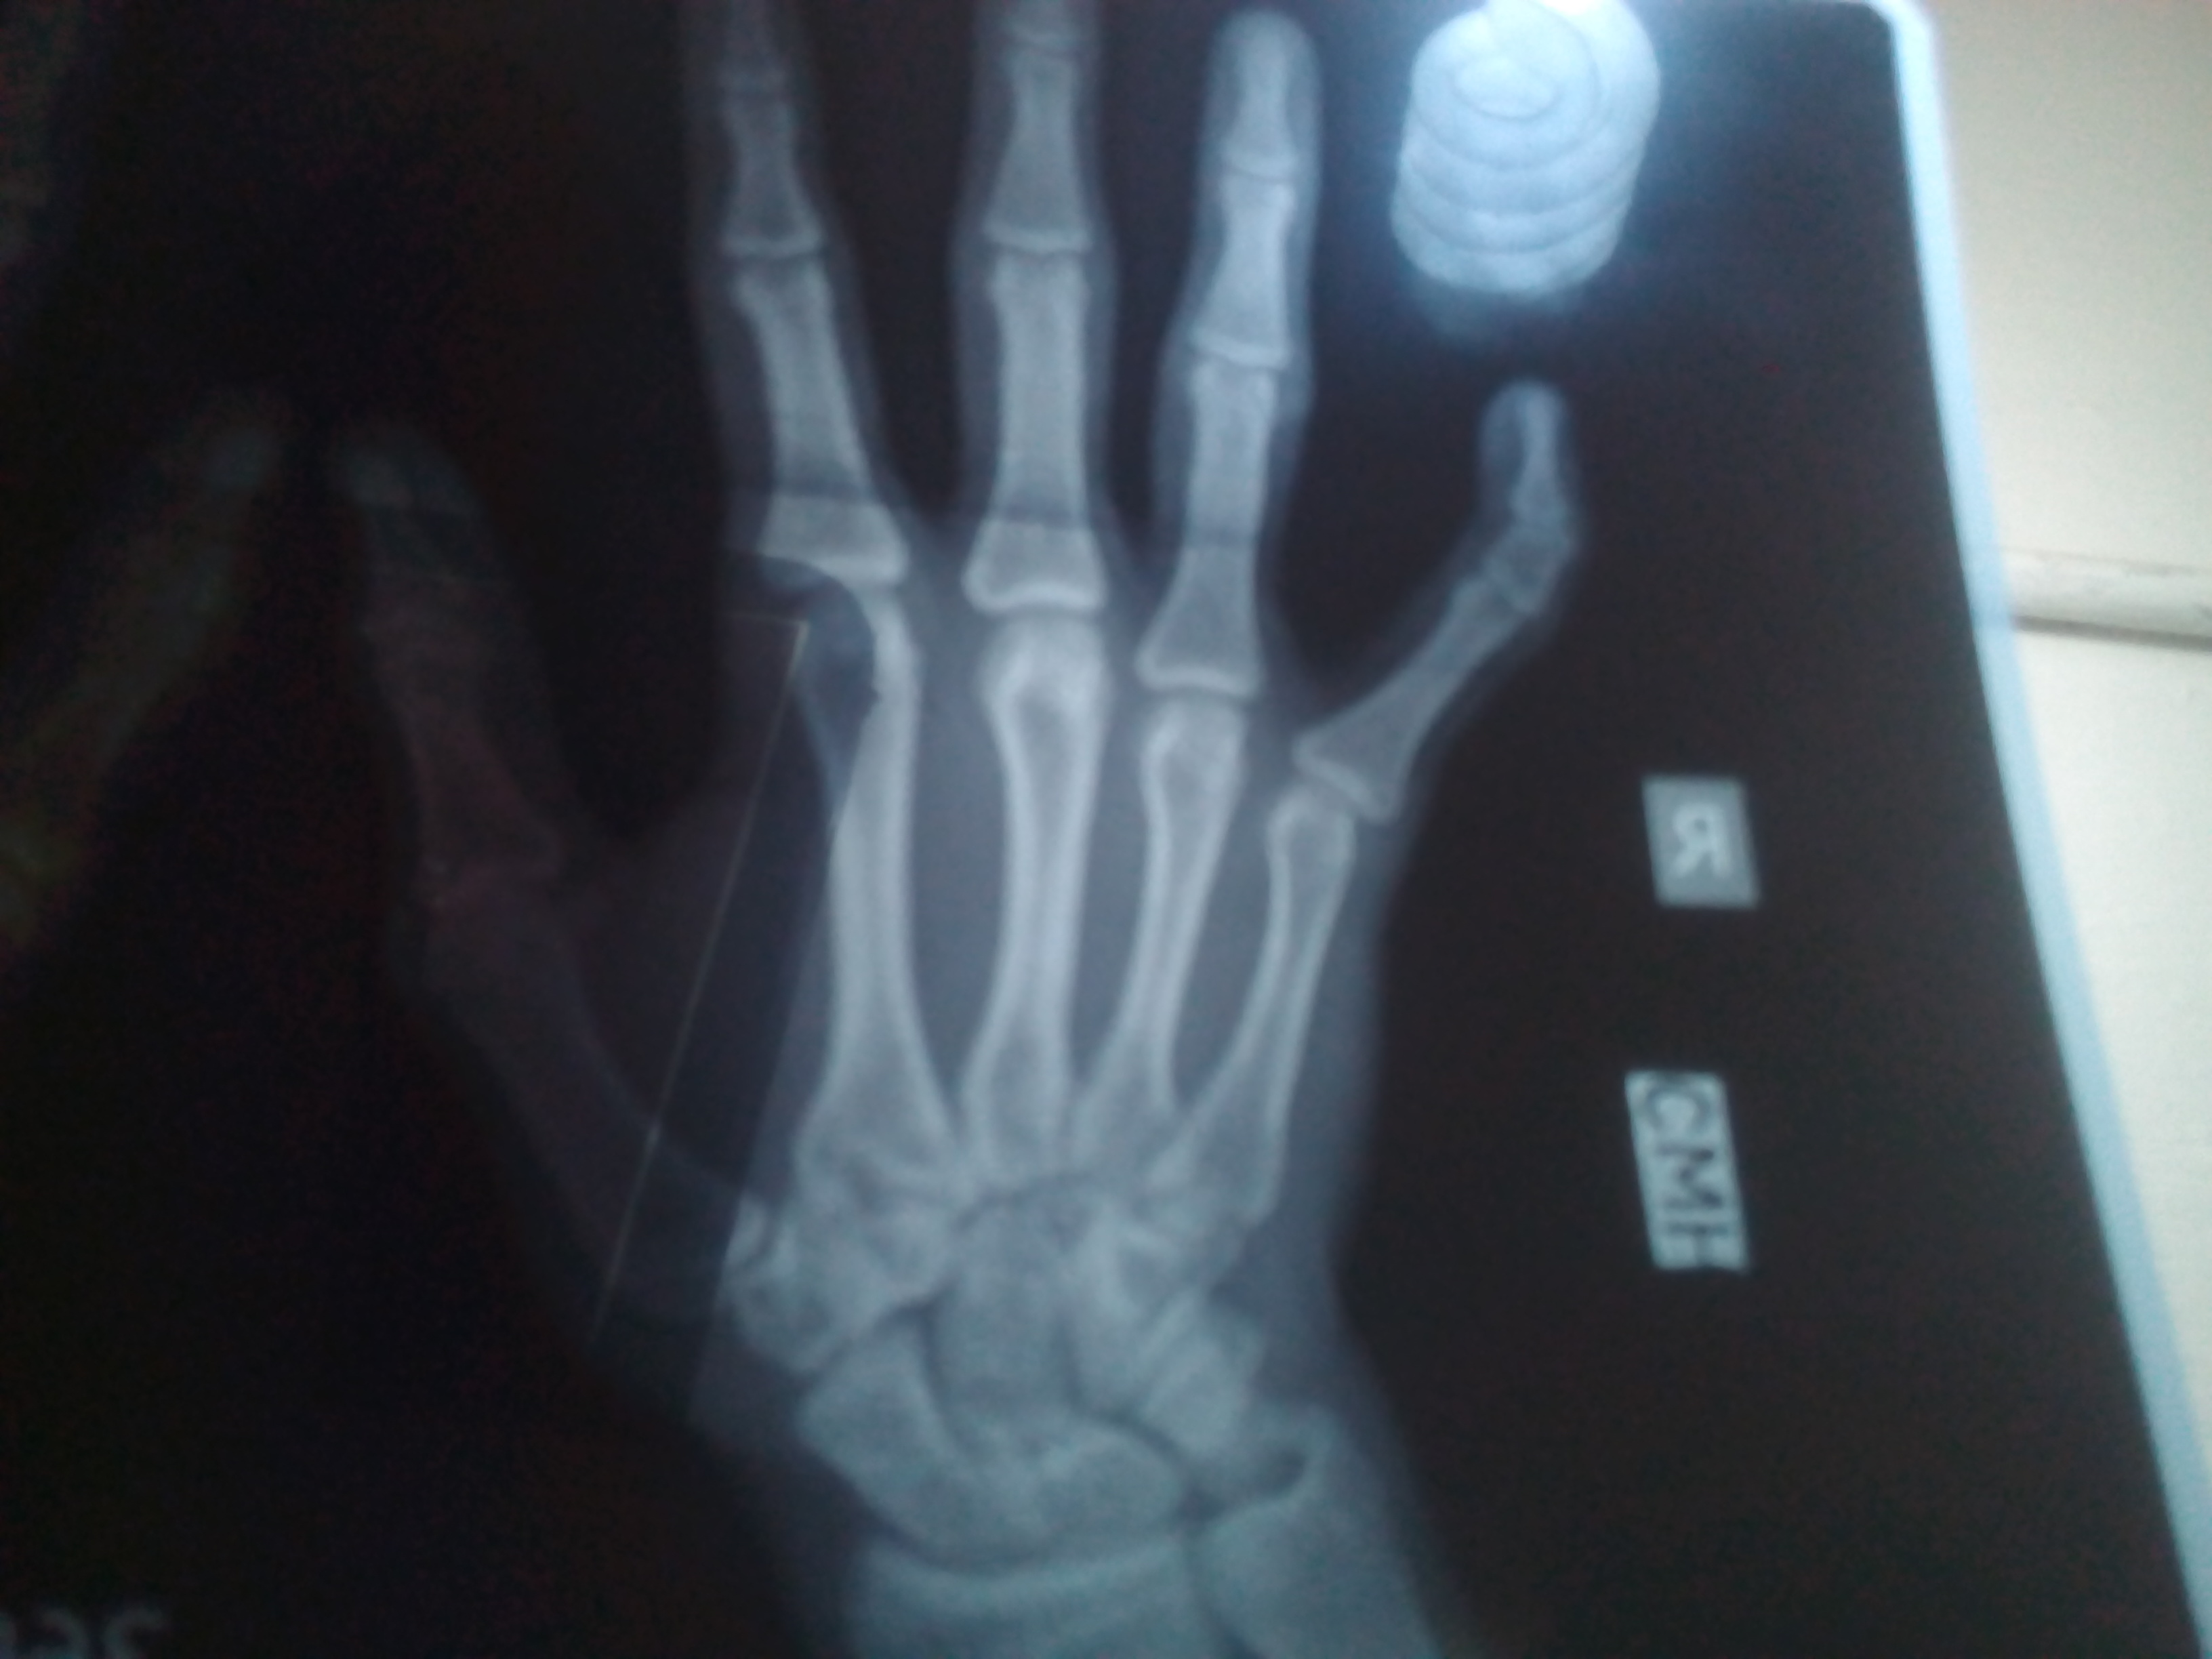

My pinky fingers of both hands are wedge shaped

it's a bony problem.

if it's hindering your function, surgery will be required to correct the deformity.

It’s by birth ignore it doesnot pose any functional problem

If your hand functions well then there is no need for surgical intervention. May be you are concerned about deformity and if so then you should consult in person as hand problems need physical examination for assessment and management.